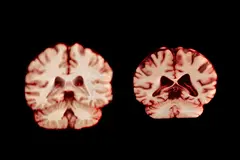

В рамках нового исследования специалисты проанализировали более 12 500 снимков мозга с помощью магнитно-резонансной томографии (МРТ) у 4726 человек. На каждого участника приходилось минимум два снимка, сделанных со средним интервалом в три года.

В целом у мужчин наблюдалось более значительное уменьшение объёма в большем количестве областей мозга по сравнению с женщинами. К примеру, постцентральная кора, отвечающая за обработку тактильных, болевых и температурных ощущений, а также за собственное положение и движения тела, у них сокращалась на 2,0%, тогда как у женщин — на 1,2% в год.